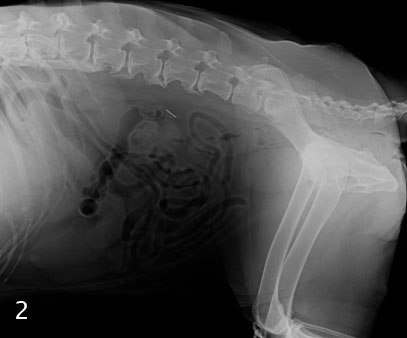

Спондилез - это заболевание позвоночника, при котором костные шпоры (остеофиты) развиваются по краям позвонков. Чтобы диагностировать это состояние, структура позвоночника должна быть исследована с помощью рентгенографии или МРТ. Чаще всего спондилез диагностируется случайно, когда у животного делают рентген по несвязанной причине. При оценке всей рентгенограммы ветеринар сможет увидеть аномальный рост костей, окружающий позвоночник. У нормального позвоночника будут отдельные «блоки» позвонков с промежутком между ними, состоящим из межпозвонкового диска. При спондилезе видны костные шпоры на концах позвонков, а в более тяжелых случ

Спондилез - это заболевание позвоночника, при котором костные шпоры (остеофиты) развиваются по краям позвонков. Чтобы диагностировать это состояние, структура позвоночника должна быть исследована с помощью рентгенографии или МРТ. Чаще всего спондилез диагностируется случайно, когда у животного делают рентген по несвязанной причине. При оценке всей рентгенограммы ветеринар сможет увидеть аномальный рост костей, окружающий позвоночник. У нормального позвоночника будут отдельные «блоки» позвонков с промежутком между ними, состоящим из межпозвонкового диска. При спондилезе видны костные шпоры на концах позвонков, а в более тяжелых случаях рост новой кости может образовывать мост над и под плавлением или связыванием позвонков.